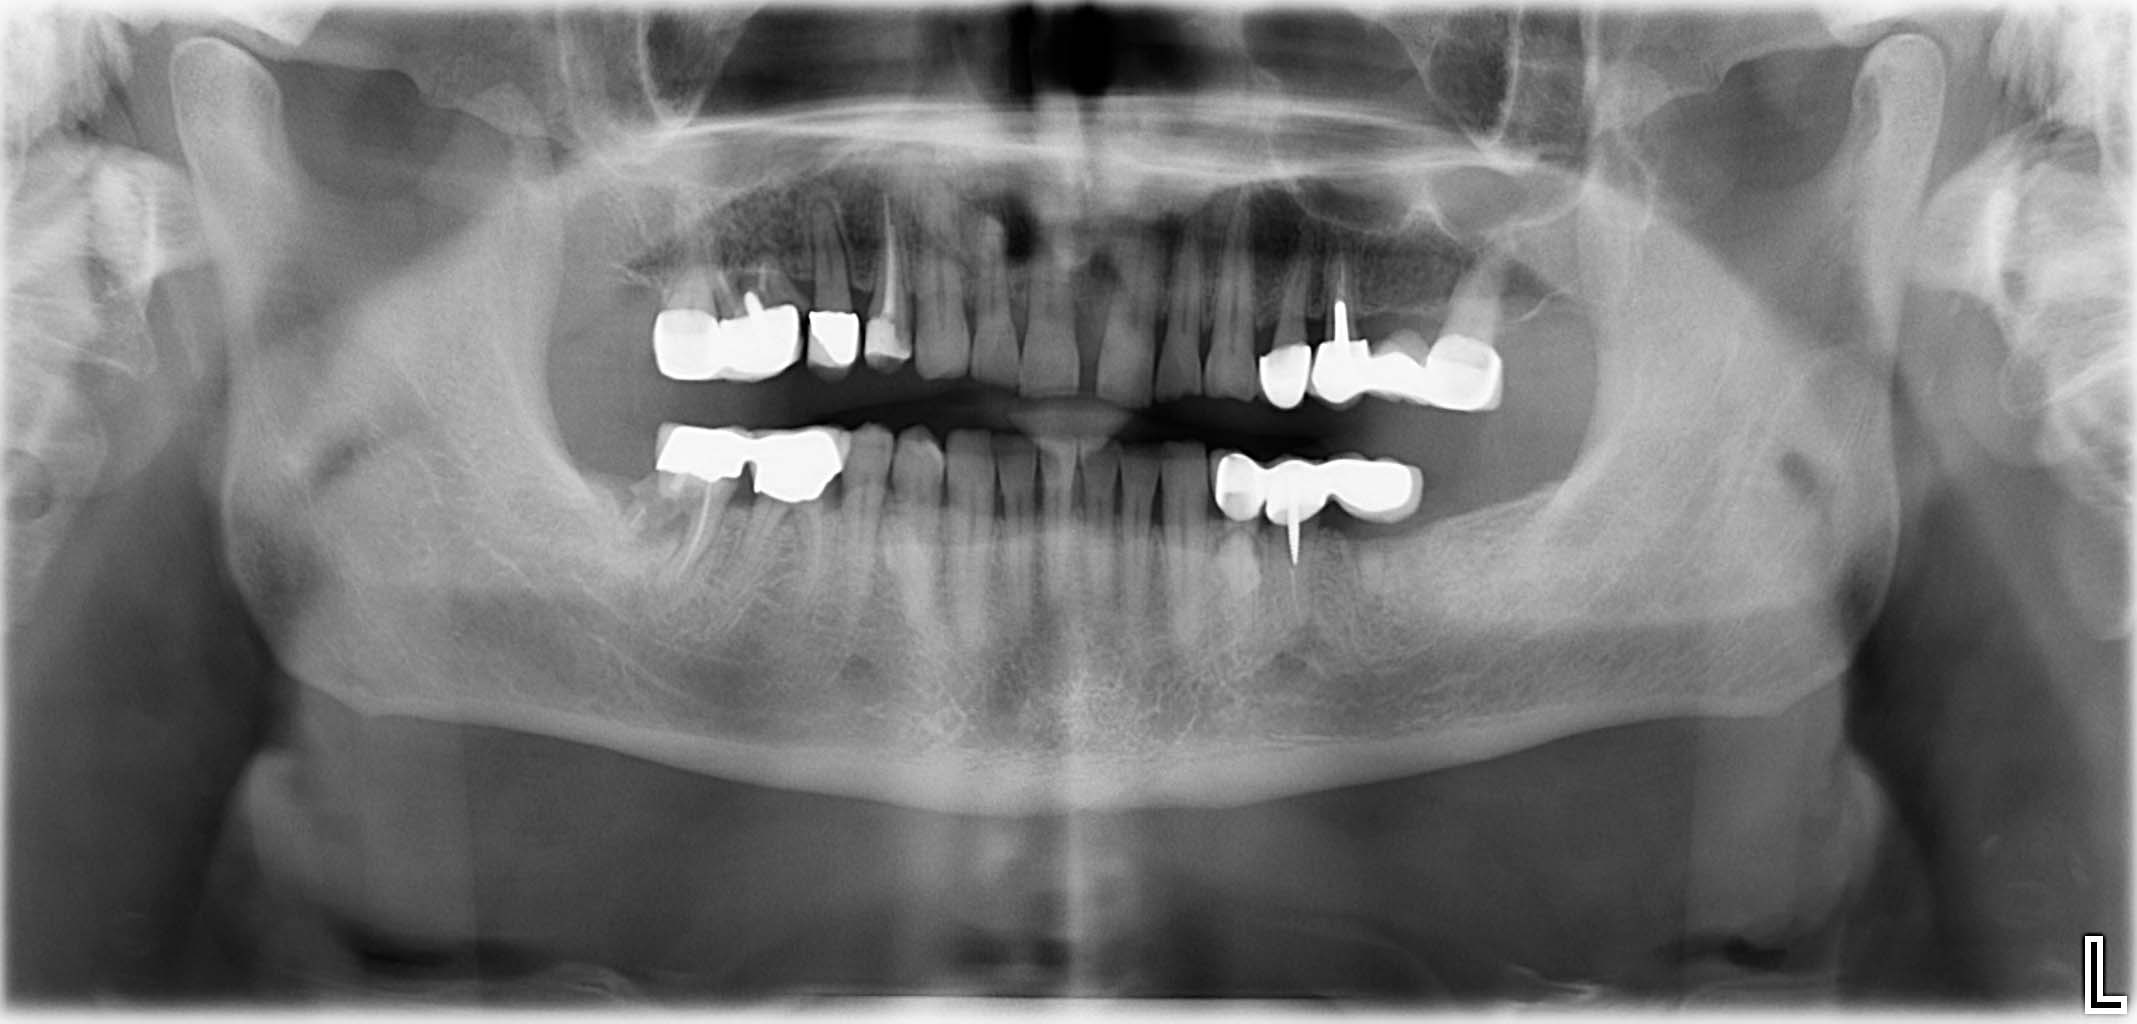

Ausgangssituation: Zahn 36 mit apikaler Beherdung, nicht erhaltungswürdig